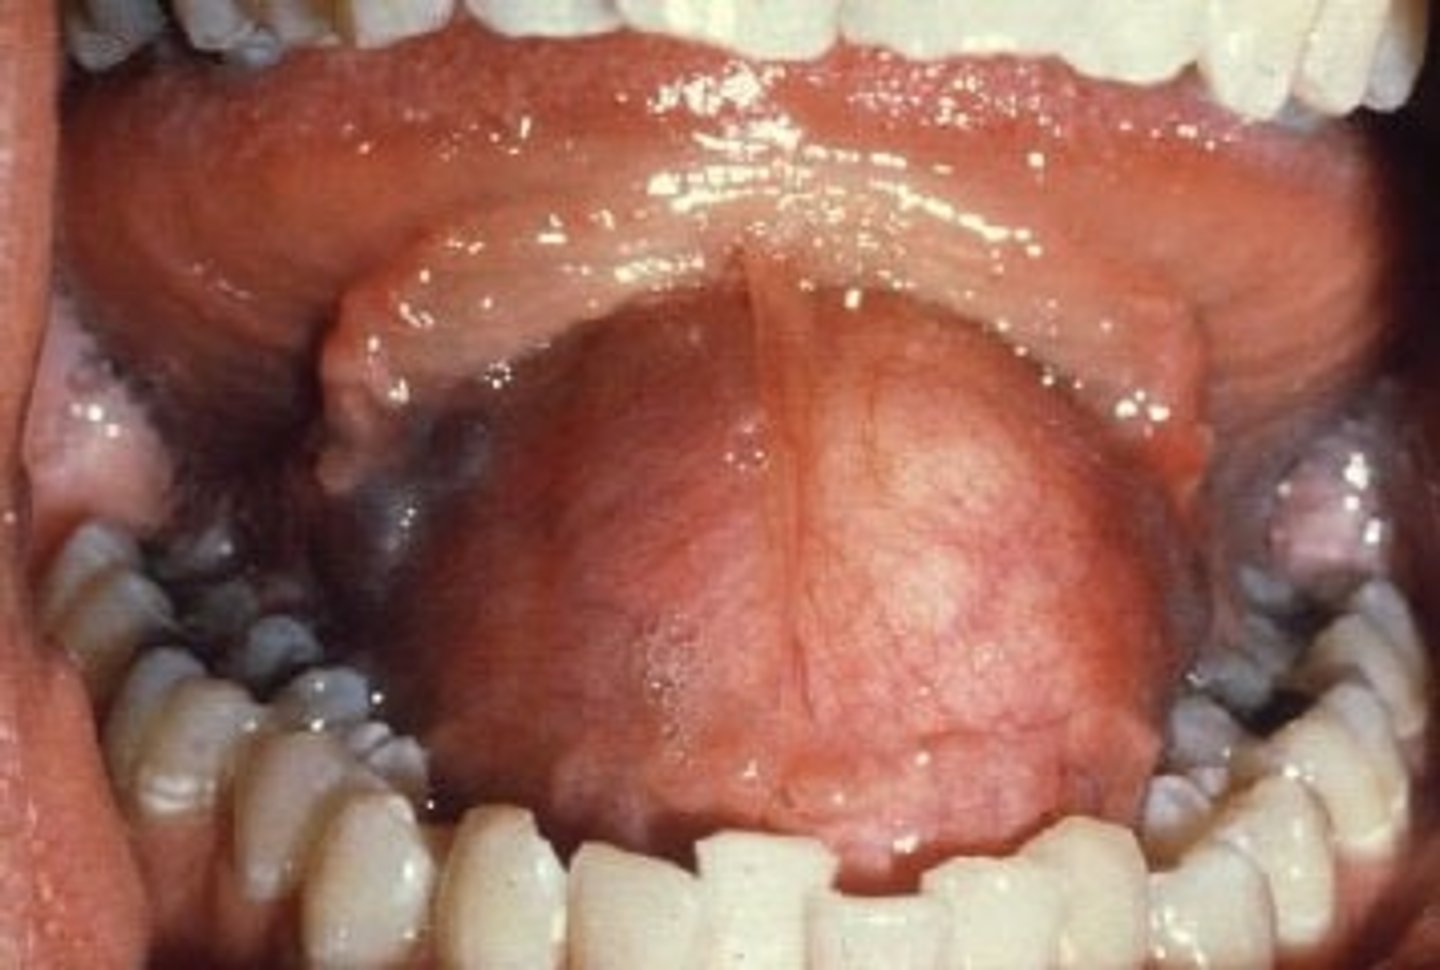

What are the common locations for Oral Lymphoepithelial Cysts?

Intraorally:

1. floor of mouth

2. ventral/posterior tongue

What are intraoral clinical features of Oral Lymphoepithelial Cysts?

well-defined pinkish-yellow raised nodule